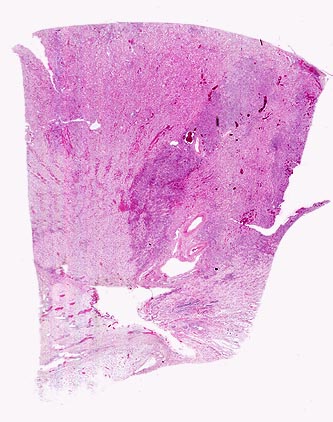

Symptomatik:

Die Patienten haben Fieber über 38°C, Flankenschmerzen, klopfschmerzhafte Nierenlager, Übelkeit, Erbrechen und ev. einen paralytischen Ileus. Pollakisurie und Dysurie können fehlen.

Diagnostik:

Die Keimzahl ist nicht beweisen für eine akute Pyelonephritis, da auch bei schwerer akuter Pyelonephritis die Bakterienausscheidung im Urin gering sein kann. Neben Urinstatus, Urinsediment, Urinkultur, Blutkultur und Laborbestimmungen sollte eine Bilanzierung der Flüssigkeits Ein- und Ausfuhr vorgenommen werden. Sonographisch können Harnaufstau, Konkremente oder Abszesse nachgewiesen und die Nierengrösse bestimmt werden.